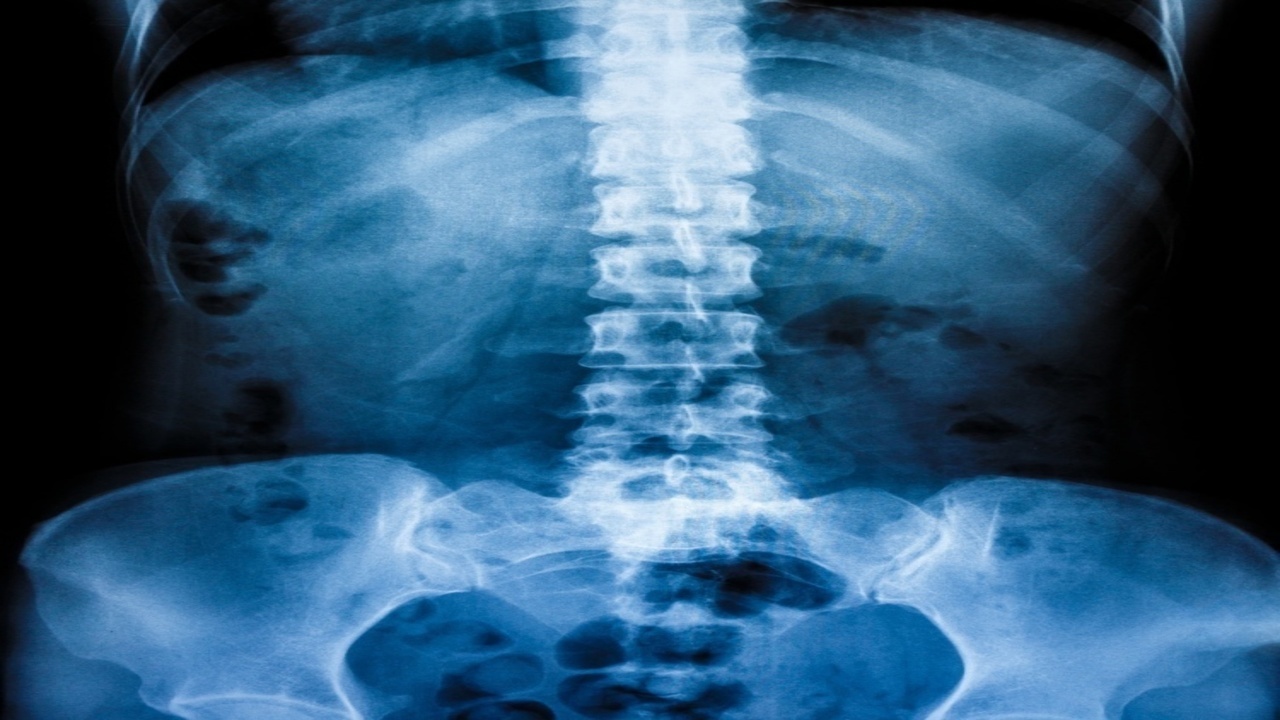

背骨(腰椎)の間には「椎間板」と呼ばれるクッションがあります。

この椎間板が潰れて中の髄核が飛び出し、神経を圧迫して腰や脚に痛み・しびれを起こす状態を「腰椎椎間板ヘルニア」といいます。

20〜50代の男性に多く、特にデスクワークや力仕事、長時間の車運転などで悪化しやすいのが特徴です。

骨盤・背骨の歪み

猫背・反り腰・骨盤の傾きで腰椎にアンバランスな力が集中。